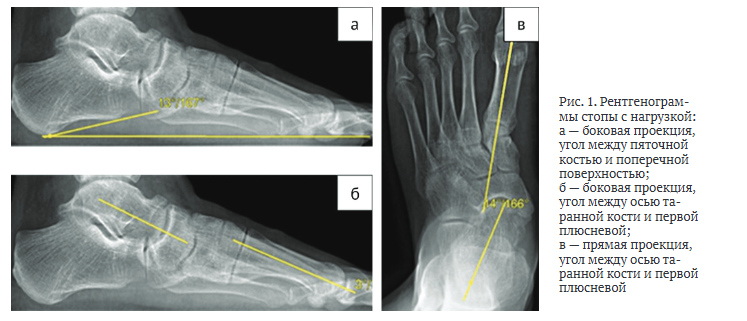

Каждому пациенту, участвующему в исследовании, при госпитализации и через год после операции проводили рентгенологическое исследование стопы с нагрузкой в двух проекциях (прямой и боковой).

На рентгенологических снимках в боковой проекции оценивали пяточно-подошвенный угол между пяточным бугром (рис. 1, а) и поперечной плоскостью, таранно-первоплюсневый угол между осью таранной кости и осью первой плюсневой кости (рис. 1, б). На прямой проекции измеряли угол между осью таранной и первой плюсневой костями (рис. 1, в). На основании измерений, проведенных до операции, оценивали степень снижения продольного свода, отведения переднего отдела стопы и вальгусную деформацию стопы, а также корригирующую способность предлагаемого метода. На следующий день после операции рентгенографическое исследование проводили без нагрузки на стопу, оценивали уровень остеотомии, положение трансплантата и металлофиксатора. Через год после хирургического лечения на контрольных рентгенограммах с нагрузкой на стопу измеряли степень коррекции деформации и ее сохранение в течение года, анализировали консолидацию области остеотомии, положение трансплантата и металлофиксатора, деформирующий остеоартроз окружающих суставов.

По результатам рентгенографии голеностопного сустава до операции получены следующие параметры: пяточно-подошвенный угол — 13°, таранно-первоплюсневый угол в прямой проекции — 14°, в боковой проекции — 3° (рис. 1). МСКТ-исследование до хирургического вмешательства не проводили. На следующий день после операции выполнили МСКТ стопы, которая выявила наличие объединённой передней и средней суставных фасет подтаранного сустава, повреждённых в ходе оперативного вмешательства (рис. 4).

Для оценки эффективности коррекции плосковальгусной деформации стопы анализировали рентгенологические снимки стопы с нагрузкой, основное внимание уделяли таким параметрам, как угол между пяточным бугром и поперечной плоскостью, таранно-первоплюсневый угол между осью таранной кости и осью первой плюсневой кости. На прямой проекции с нагрузкой изменялся угол между осью таранной и первой плюсневой костями.